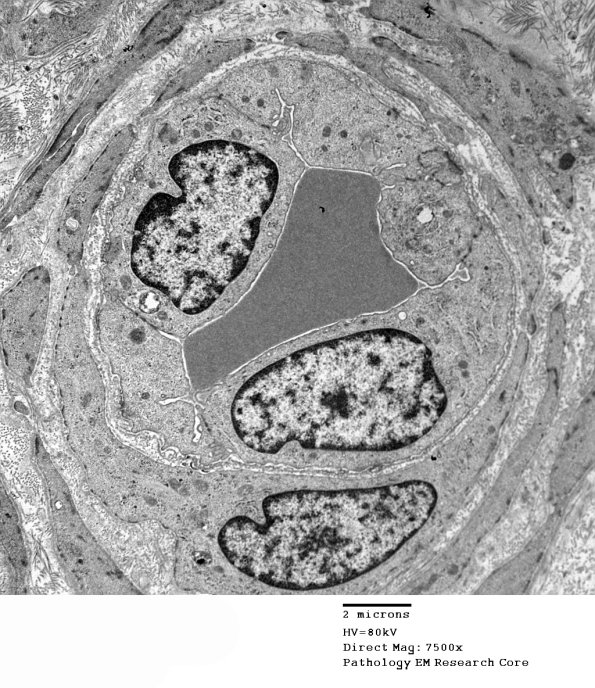

It is not unusual to see small venules with prominent endothelial cells. (electron micrograph)